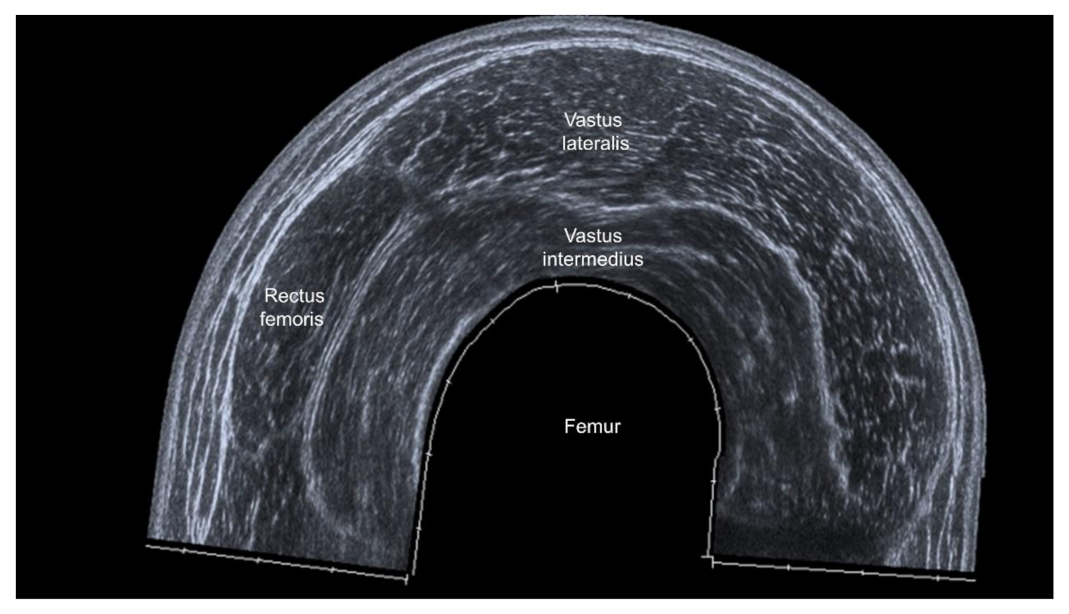

3.4.2. Sites of Muscle Measurement

3.4.3. US parameters in B-Mode